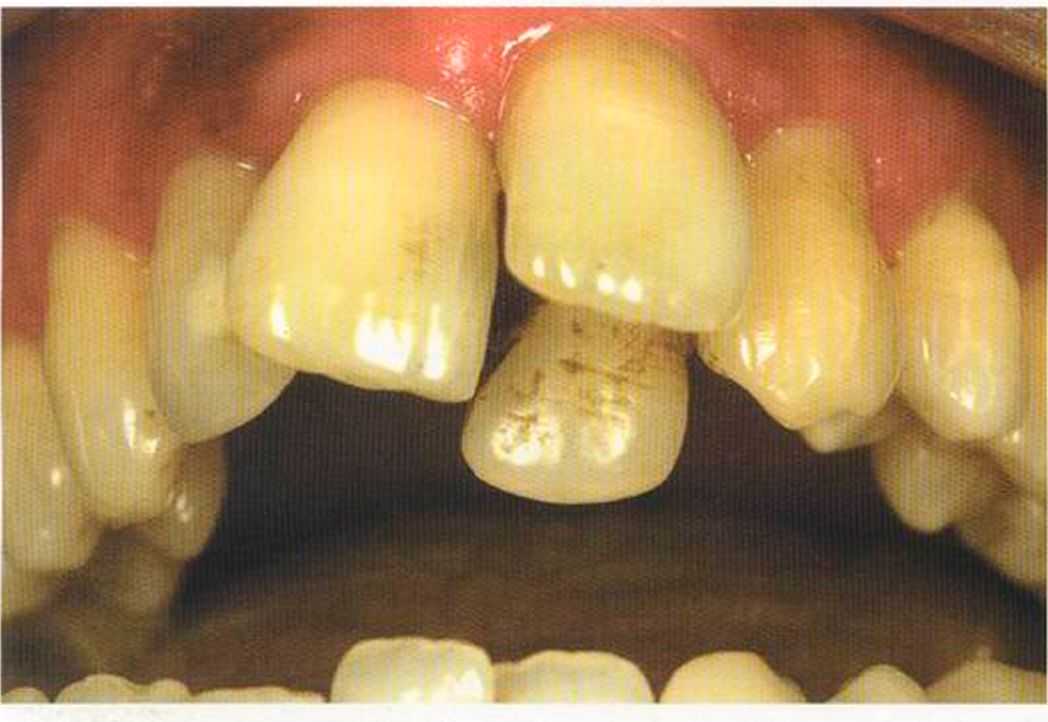

Первое лечение проходию много лет назад у другого доктора. Со временем ос те пи / ка уху дин ьась, особенно в пришеечной области. Этот пациент хотел новые коронки в области 12 и 22, по сомневсься, нас кол ько хорошо они будут выглядеть.

Результат с использованием In-Ceram развеял все сомнения, и решение об изготовлении коронки на другой боковой резец не заставило себя долго ждать.

После того как мы определит цвет зуба, решено быо сначсьа изготовить одну коронку.